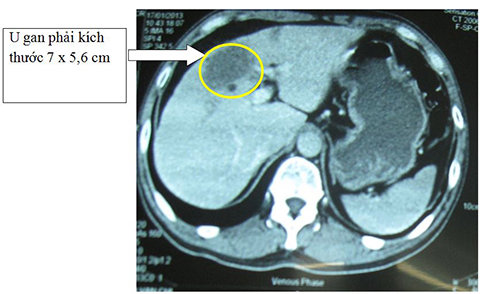

Trước sự phát triển của nền y học, nhiều thành tựu về y khoa đã được ứng dụng trong việc thăm khám, chẩn đoán bệnh, mang lại nguồn sống cho nhiều người. Đây là tin đáng mừng cho những ai đang mắc những căn bệnh khó chẩn đoán như bệnh gan. Trong đó, chụp cắt lớp gan là kỹ thuật được chỉ định phổ b...